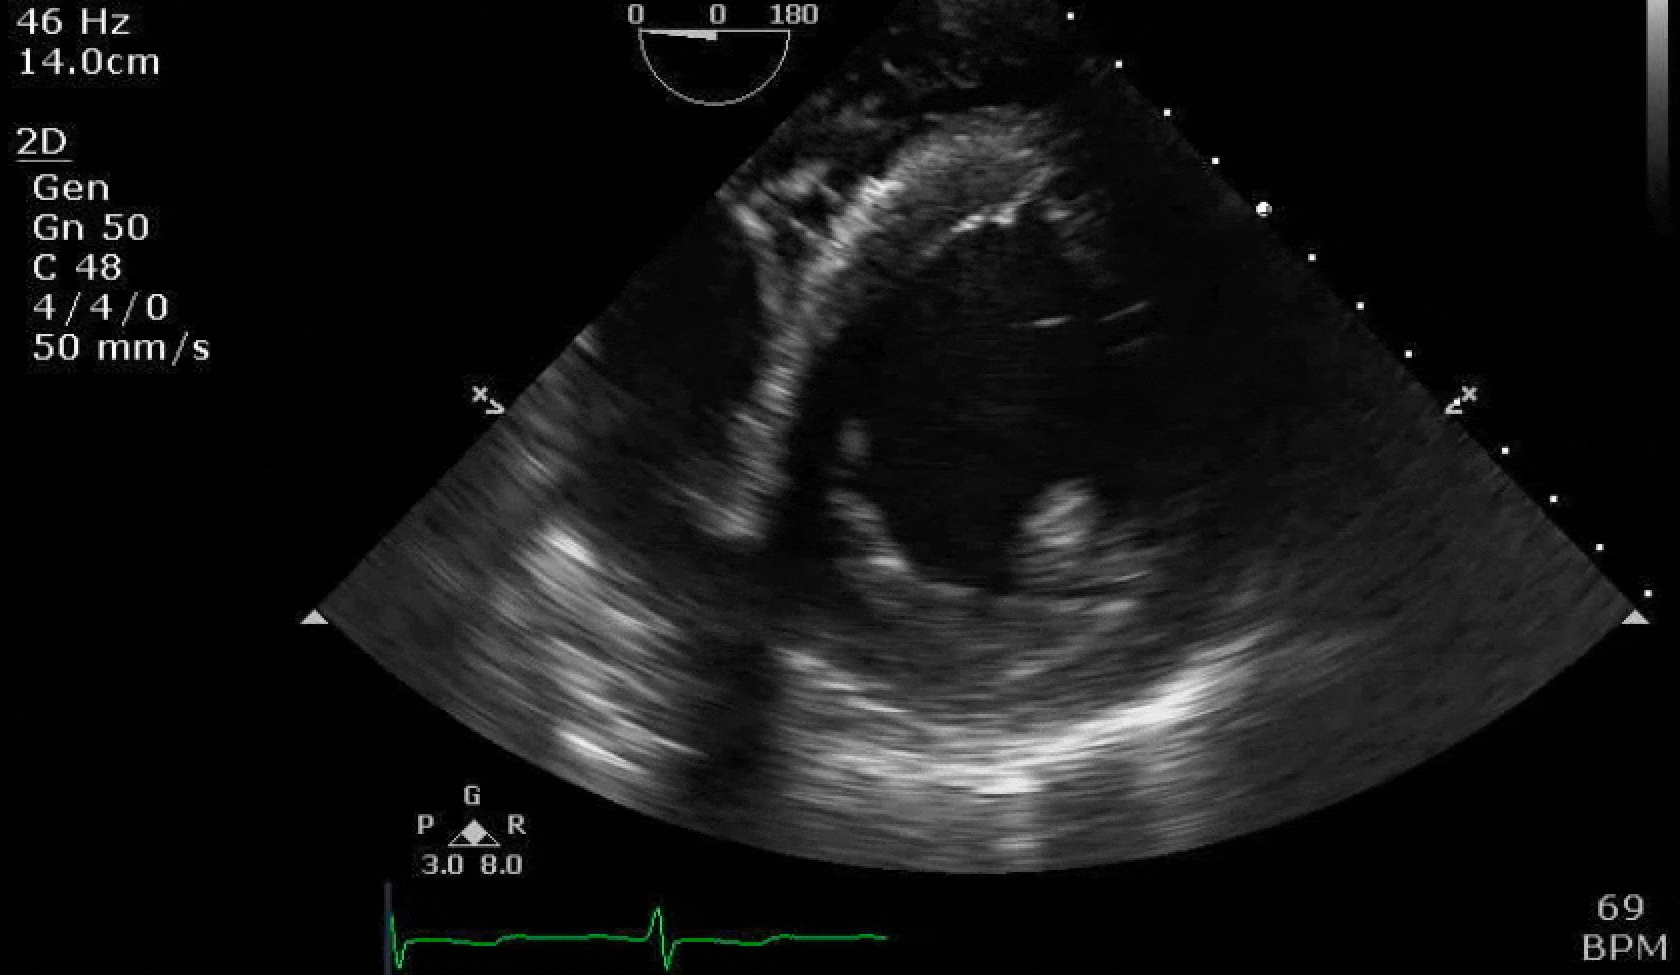

70 yo M, blue collar worker (active at baseline), no reported PMH, never seen a doctor. Walks into the ED with 3 day hx of dyspnea and 2-3 weeks of new lower extremity edema. Also has a URI. HR 101, BP 97/55, satting 96 on RA. Super high BNP, negative trop. Admitted for new HF. CT chest shows incidental 5.0 cm ascending aorta and also small pleural effusions.

Here are some TTE instead of TEE images for a change.

What else do you need to know? Any other workup? What specific inferences can be made from the mitral inflow, atria size, and strain pattern? What are our treatment options?